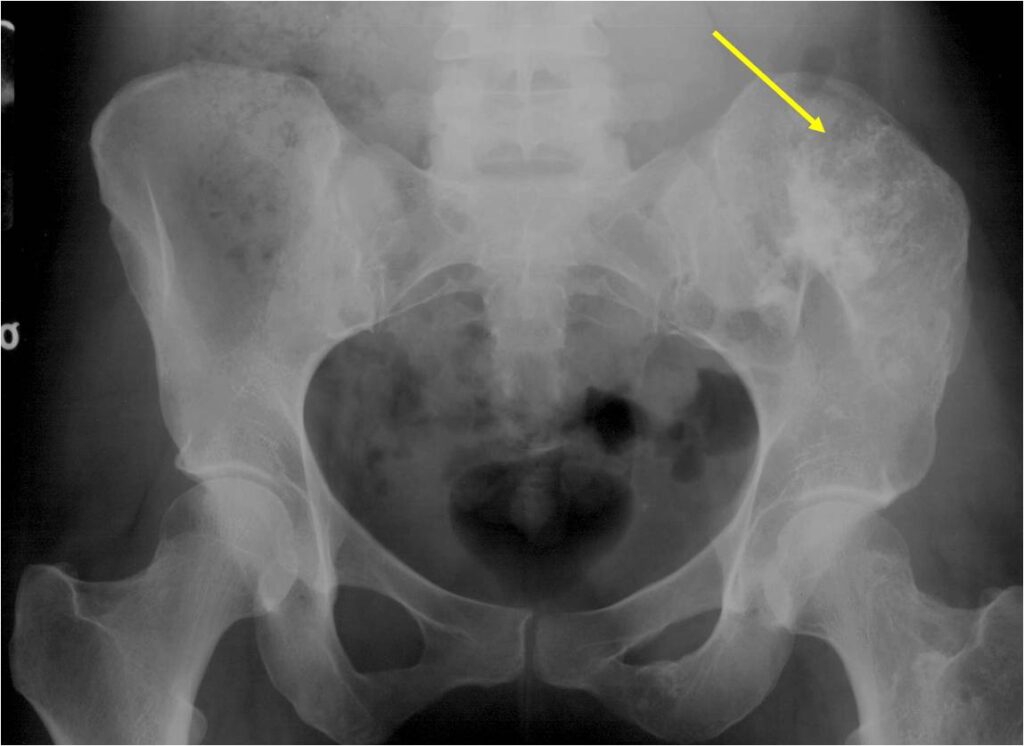

- Enchondromas of the pelvis, vertebrae and ribs are uncommon

- Almost all hyaline cartilage tumors of the pelvis are considered malignant based on anatomic location no matter what the pathology shows. These tumors will ultimately grow locally and have the potential to dedifferentiate or change into a higher grade chondrosarcoma.

- Localized, radiolucent defect usually with punctate calcifications

- Calcifications are stippled, punctate, popcorn like calcifications and “Ring and Arc” calcifications

- Chondroid matrix with calcifications in majority of tumors